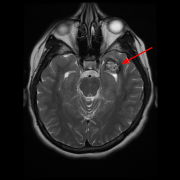

脑海绵状血管瘤,有必要手术吗?为了诊断对于海绵状血管瘤,主要使用磁共振成像,其中这些病变显示典型的“爆米花”外观,低信号周围有晕圈。我们...

脑海绵状血管瘤无症状或者偶然发现,需要手术吗?脑海绵状血管瘤常会因非特异性或无关症状而做影像学检查时被发现(图1)。对于无症状的脑干海绵状血...